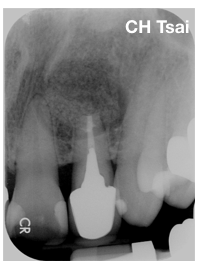

當次手術的治療內容,主要在局部麻醉下進行,在顯微鏡下先定位骨破壞的位置、清除發炎組織並送檢,接下來進行牙齒根尖的切除,並進行超音波根管的清創及使用特殊的生物相容性高之封填材做根尖的逆向充填。

因骨頭的破壞範圍廣泛,於是在骨頭破壞位置,除了進行徹底的清創,也放置了骨粉及再生膜,促進齒槽骨再生的潛力。